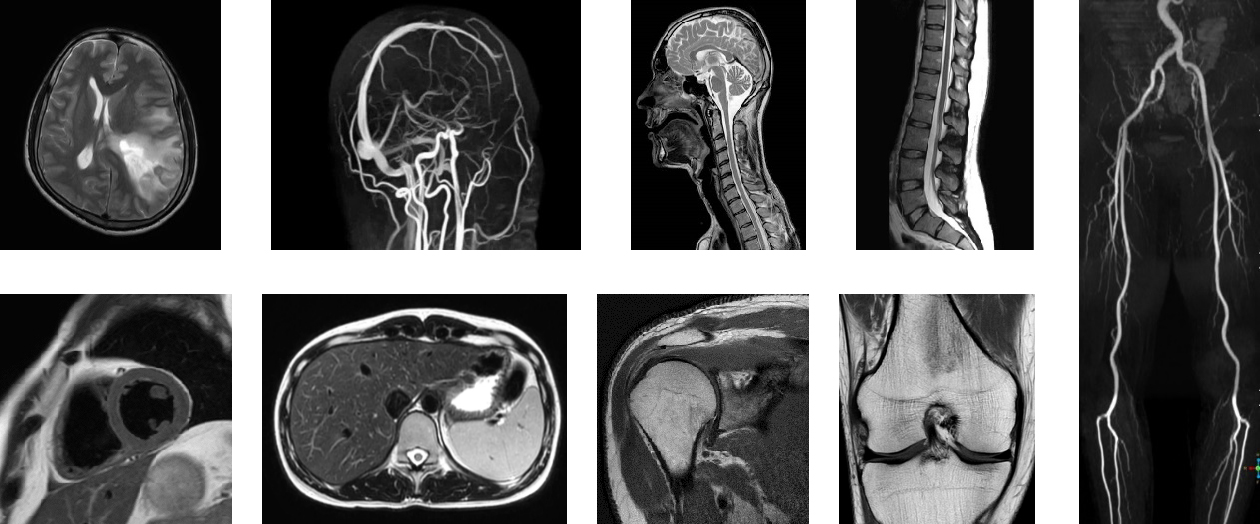

MRI画像

当院では最高磁場3.0テスラの最新鋭MRI装置を導入しておりますが、患者さんの条件よっては(体にプレートなどインプラントを埋め込んでいる方など)検査制限がありました。

この度、当院はさらにオランダ国フィリップス社製のMRI装置Ingenia Prodiva 1.5テスラという最新鋭の装置を導入いたします。1.5テスラは磁場強度が3.0テスラよりも低いので、体内にインプラントを入れている患者さんでも安全に検査を受けていただける装置でございます。これにより、当院では検査を受けられなかった患者さんにも検査を受けていただける環境を整備いたします。

本装置は最先端のデジタルテクノロジーにより短時間で鮮明な画像を得ることができ、より正確で多くの情報を元に確信のもてる診断が可能になります。

またMRIに入る患者さんの負担にも着目しており、検査時に装着するRFコイル(信号受信器)が従来よりも軽量化されております。軽量化によりセッティングにかかる時間のストレスや従来のコイルでは重いと感じられていた患者さんの負担軽減に貢献いたします。